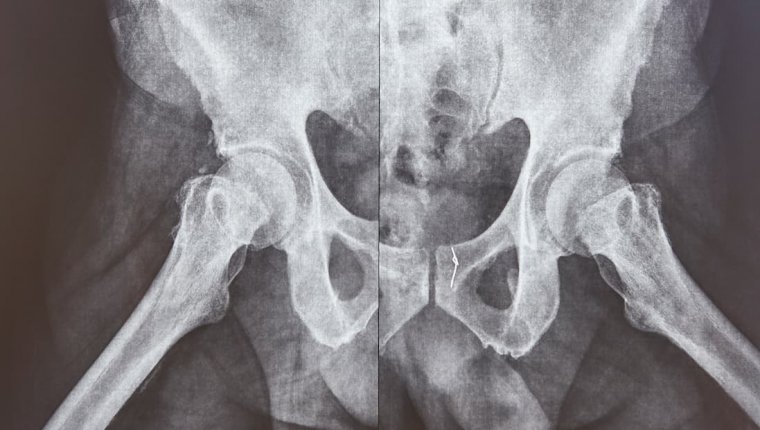

Jednymi z najczęstszych przyczyn są problemy związane z siedzącym trybem życia (przyjmując długotrwale pozycję statyczną, doprowadzamy do uciskania nerwów, co owocuje nieprzyjemnymi dolegliwość) oraz związane z zaburzeniami układu kostno-stawowego. To ostatnie dotyczy osób które, mimo że na co dzień pozostają aktywne fizycznie, cierpią na zespół bólowy miednicy, bo ruch uwidacznia zwyrodnienia, skrzywienia kręgosłupa (tj. skolioza), czy konsekwencje przebytych złamań.

Ból miednicy po upadku

Jeszcze innym rodzajem bólu, który może być związany z miednicą, a którego nie należy bagatelizować, jest ból po stłuczeniu. W wyniku wypadku, może dojść nawet do złamania miednicy. Gdy bólowi towarzyszy obrzęk i zasinienie tej okolicy oraz jeśli ból nasila się przy ruchach kończyn i obserwowalne są zniekształcenia obrysów miednicy gołym okiem, należy jak najszybciej udać się do lekarza.